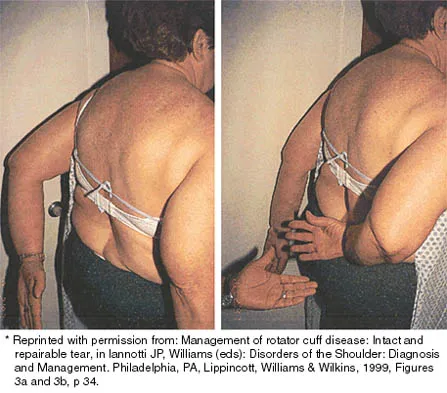

The condition shown in Figures 9a and 9b is most likely the result of

Explanation